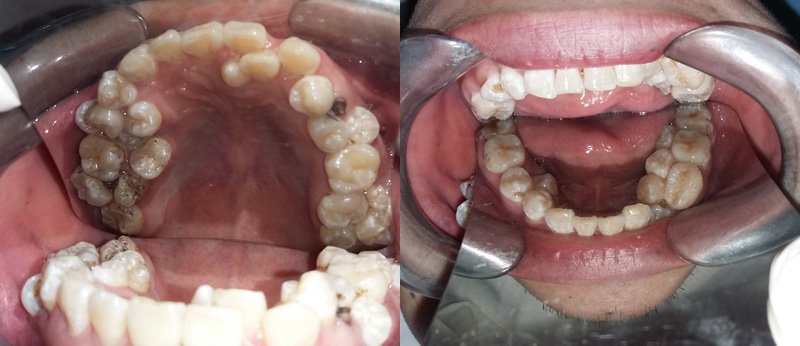

Đây là một trường hợp rất hy hữu từ trước đến này. Anh Đỗ Văn Sơn đã làm các bác sĩ hoảng hốt vì anh thừa tới 17 chiếc răng.

Anh Sơn cho biết, từ năm 15 tuổi đến nay, cứ mỗi năm anh lại thấy mọc thêm 1 chiếc răng. Nghĩ là mọc lẫy bình thường, lại không đau đớn nên anh không hề đi khám. Cách đây 10 ngày, thấy răng sâu ở hàm trên đau nhức khó chịu, anh mới đến Bệnh viện Việt Nam – Cu Ba khám.

Tại đây các bác sĩ đã hết sức bất ngờ khi phát hiện ngoài chiếc răng sâu, bệnh nhân bị mọc thừa đến 13 chiếc răng ở vị trí răng 4 và 5 trên 2 hàm. Các răng mọc lệch, chen chúc, dàn hàng ngang khiến việc vệ sinh khó khăn, gây sâu, viêm tủy.

Theo BS Thái, trường hợp thừa nhiều rằng nhất đã từng gặp là 8 chiếc, riêng trường hợp anh Sơn thừa đến 17 chiếc răng thì chưa gặp bao giờ. Qua trường hợp trên, BS Thái khuyến cáo, người dân nên có thói quen khám răng định kỳ 6 tháng 1 lần. Khi thấy răng mọc 2-3 cái một chỗ cần đi khám ngay để can thiệp kịp thời.